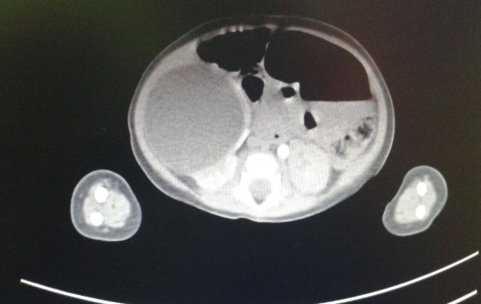

Рис.2 Травма живота: разрыв полого органа

Внутривенная урография по экстренным показаниям проводилась у 9 детей, в 2-х случаях диагностирован разрыв почки.

С целью дифференциальной диагностики и выбора оптимальной тактики лечения в 107 случаях была проведена компьютерная томография органов брюшной полости, забрюшинного пространства и таза. Данная группа по результатам исследования распределилась следующим образом: